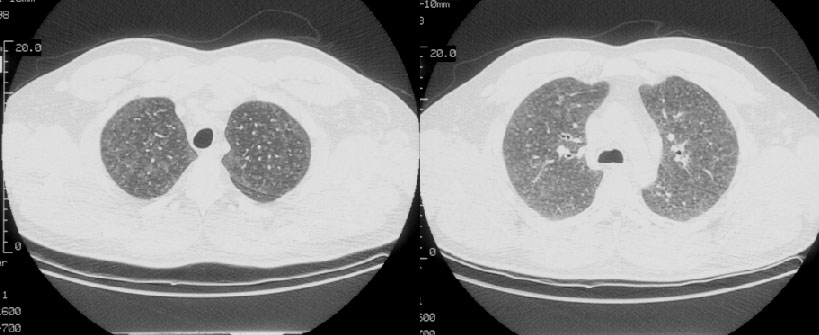

Scott WilliamsMiscellaneous PulmonaryMiscApril 2, 2002Mediastinal MassesMediastinum > ForegutcystApril 2, 2002CongenitalCongenital > SequestrationApril 2, 2002Collagen VascularCOLLAGEN VASCULAR DISORDERSApril 2, 2002Tumor ImagingTumor > ProstascintApril 2, 2002PulmonaryPulmonary > Other lesionsApril 2, 2002Nuclear MedicinePET > PET tumor imaging > Colon CancerApril 2, 2002Inhalation-LungsInhale > EAA > ImagesApril 2, 2002CardiacCardiac > Congenital > HemitruncusApril 2, 2002AutoimmuneAutoimmune > IPFibrosis > DIPimages > Case1April 2, 2002Previous PagePage 95 of 265Next PageTop StoriesCT5-year CTC screening interval is appropriate for colorectal cancerThe study's findings add to an ongoing conversation about the use of CTC for colorectal cancer screening.MRIASTRO: Daily MRgRT recontouring improves prostate treatment outcomesRadiation Oncology/TherapyASTRO: Radiation therapy comparable to surgery for early-stage lung cancerCTCT use in the ED has more than doubled over a decadeSponsor ContentDigital Innovations Shaping the Future of Radiology